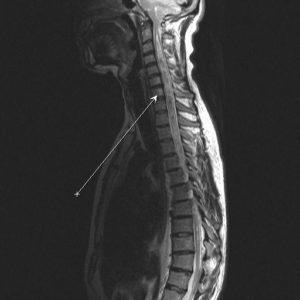

Процесс диагностики включает в себя множество последовательных снимков, сделанных в трех взаимоперпендикулярных плоскостях. Каждая серия снимков занимает около нескольких минут. Общая продолжительность процедуры не превышает 45 минут. На представленном изображении, сделанном во время МРТ, видны грудной, поясничный и шейный отделы спинного мозга.